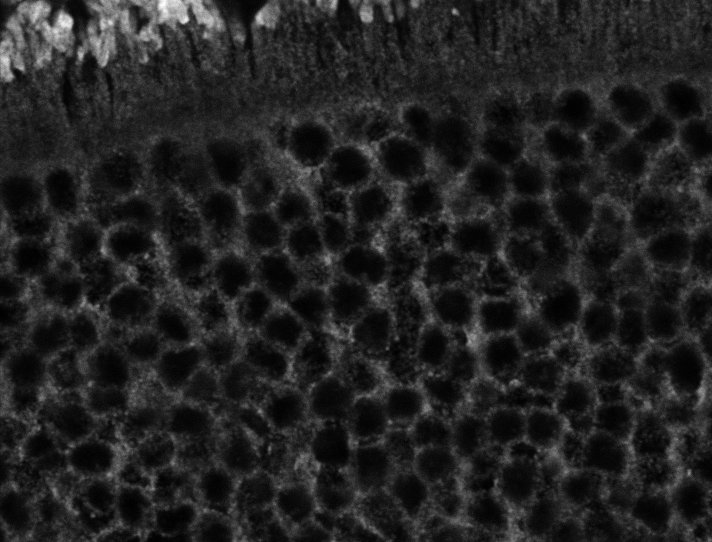

Healthy Retina

Healthy Choroid